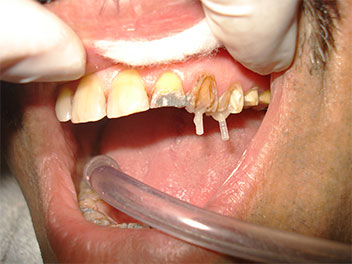

Re-Construction of broken tooth with post and core